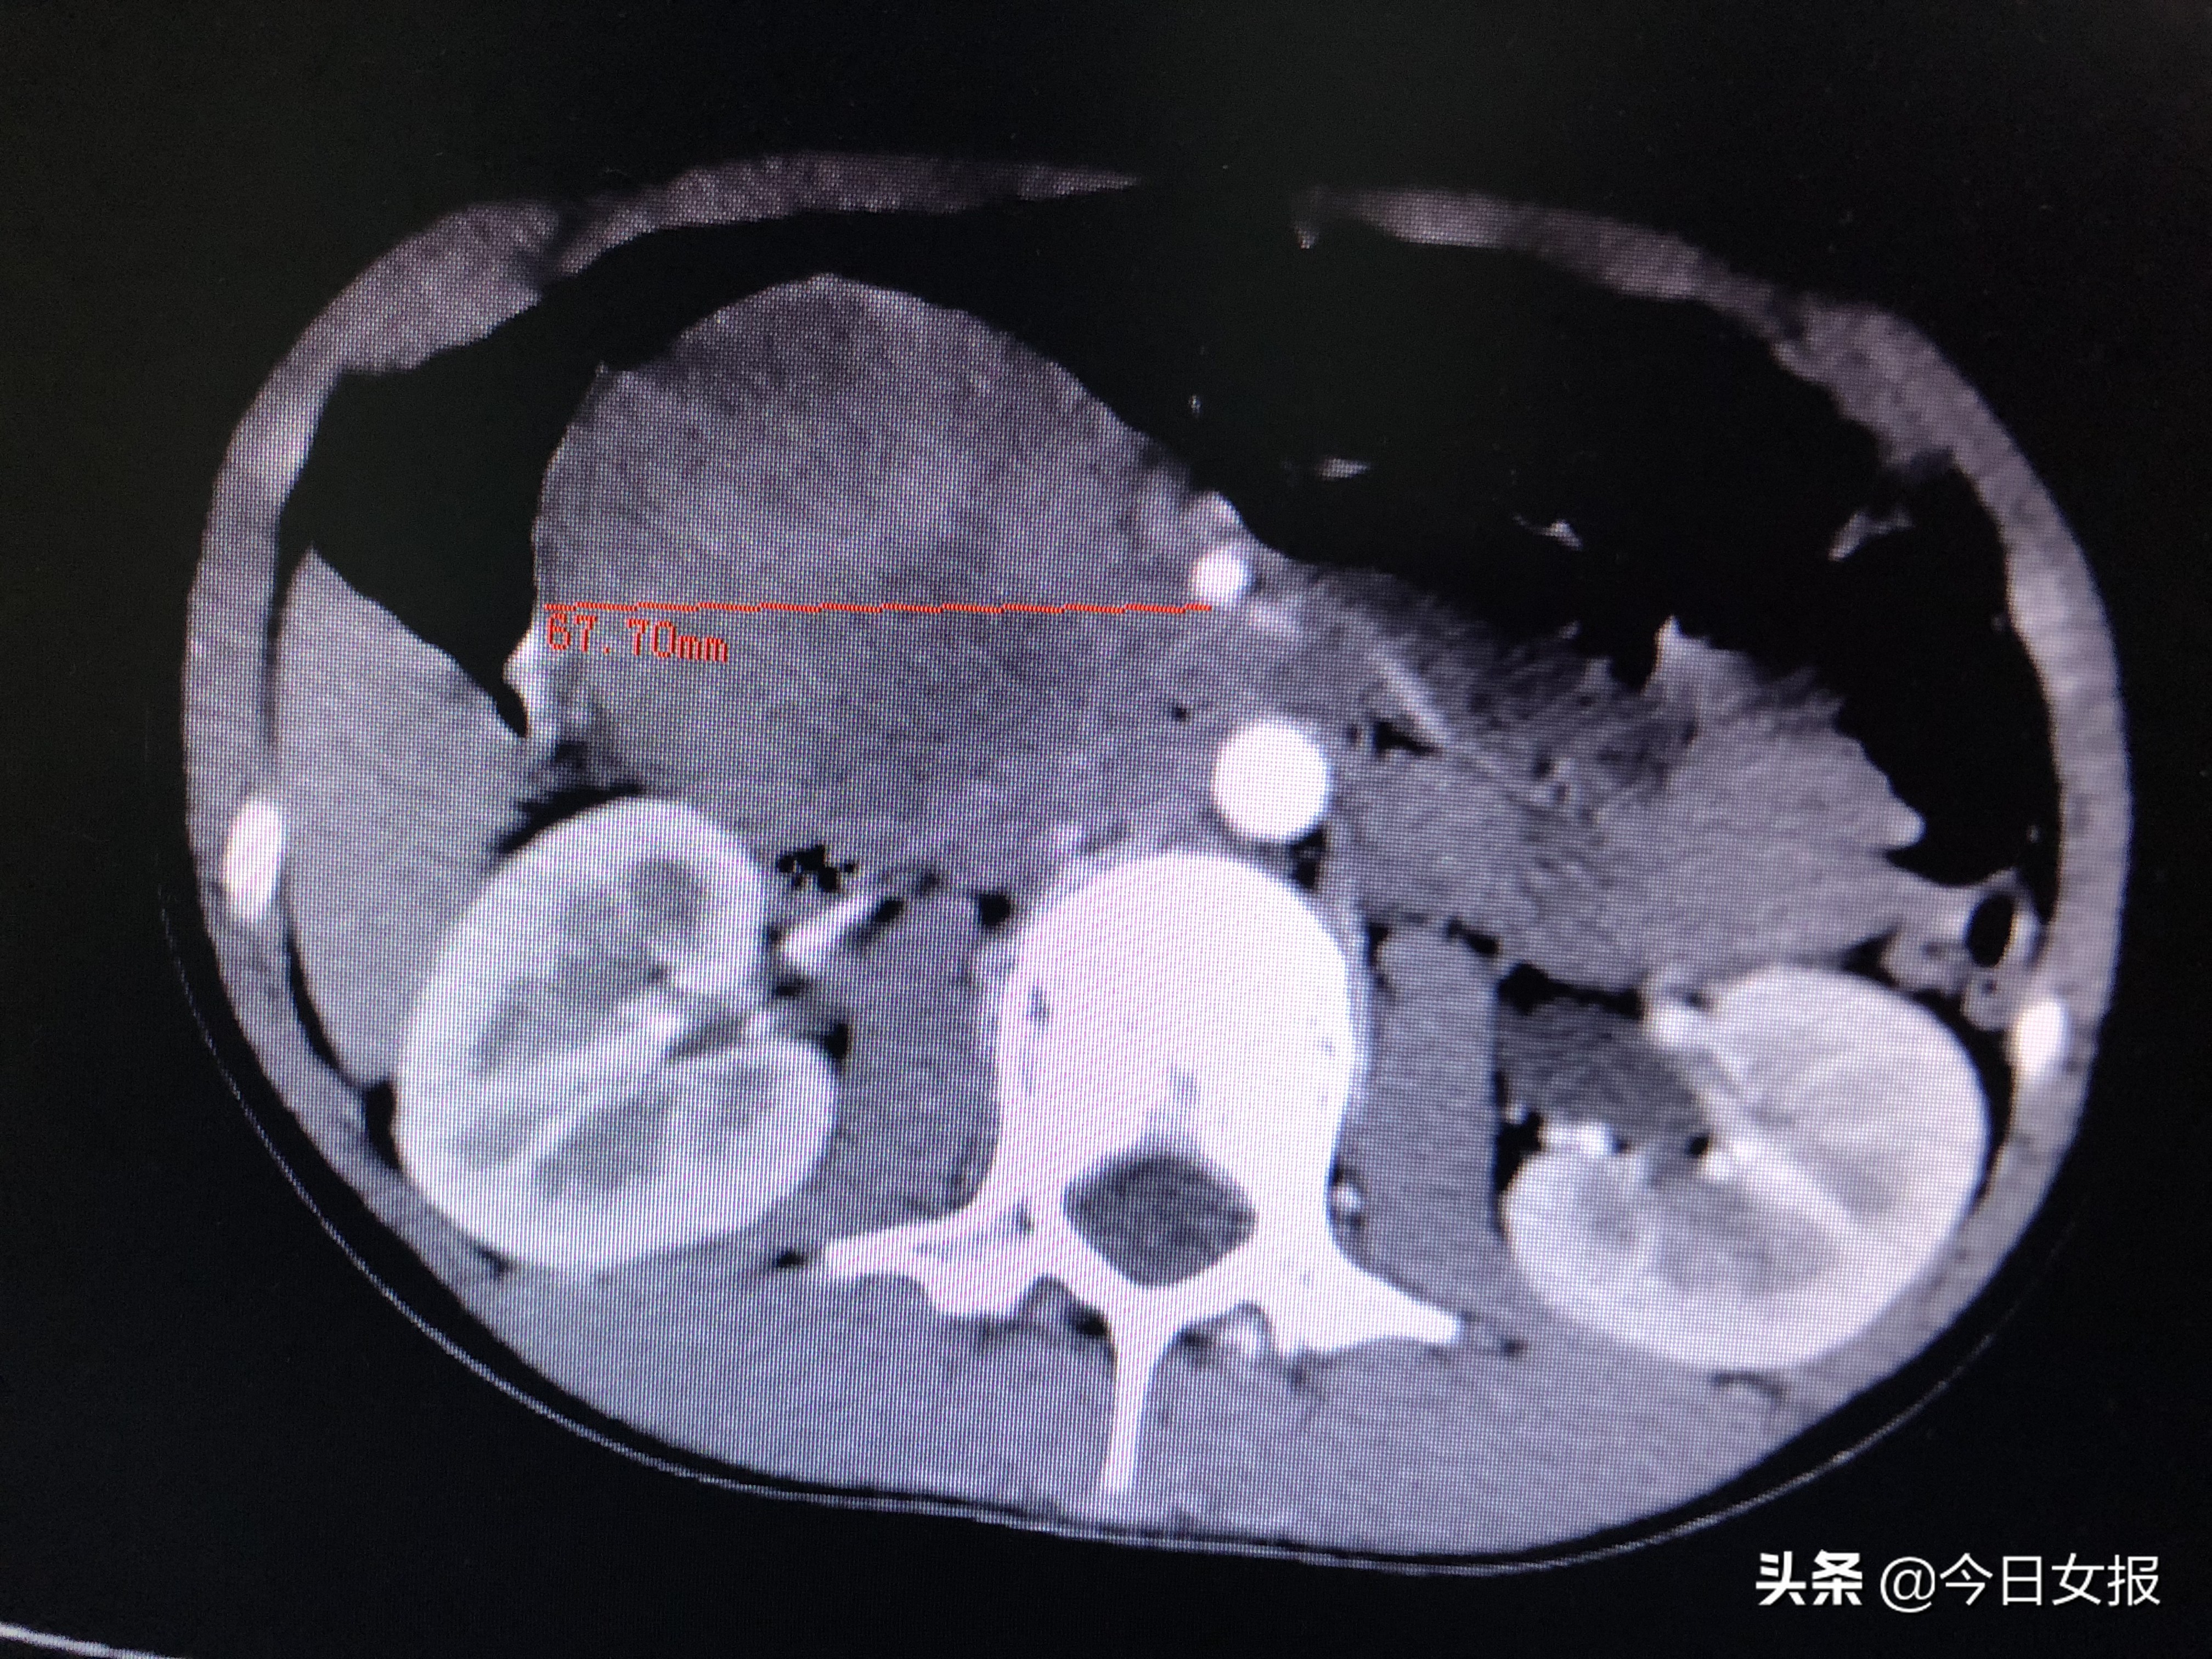

10岁的婷婷(化名)来自湖南省永州市冷水滩区,2019年4月12日上午,她在课间操时与同学一起踢毽子,被一名男同学不小心踢到肚子。不长后,婷婷感到上腹部剧烈疼痛,随后出现恶心、呕吐的情况,吃不了东西,连喝水都吐。家长闻讯后将她送到当地医院,做了腹部超声、CT等检查后被告知,婷婷的胰头部位长了个“很大的东西”,建议前往长沙进一步治疗。

4月17日晚上7时许,在完善相关检查进一步明确病情并排除手术禁忌后,由蒋波、陈梅福、成伟等专家组成的手术团队为婷婷施行急诊全麻下腹腔镜胰十二指肠切除术。术中发现,肿瘤压迫十二指肠、结肠,且出血后粘连严重,腹腔镜下分离难度极大;同时,肿瘤与肠系膜上静脉、肠系膜上动脉、门静脉等重要血管紧邻,一不小心就容易损伤这些大血管,手术风险和难度不言而喻。所幸在专家团队的高超技艺和谨慎操作下,手术于次日凌晨3时许顺利结束,切下的肿瘤达67×61×50mm3,病理检查证实为“胰头实性假乳头状瘤并出血”。